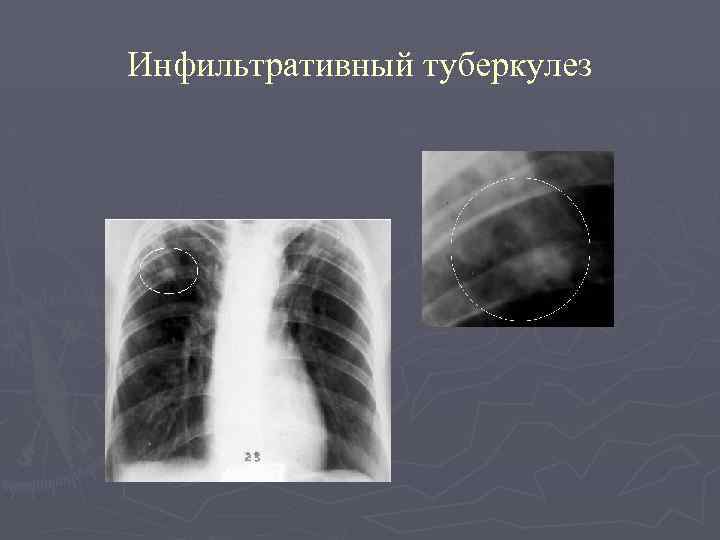

Симптомы и лечение инфильтративного туберкулеза легких

Раздел: Снимки-откровения